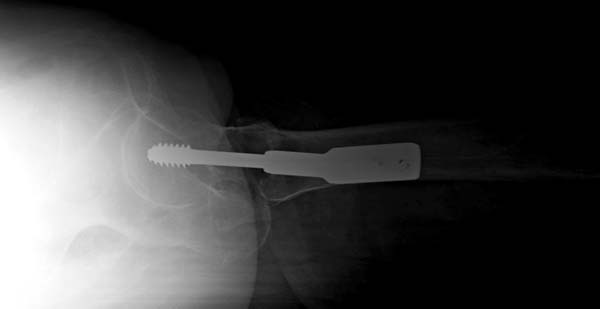

Сейчас на рынке много минимально инвазивных имплантов для фиксации чрезвертельных переломов.

При невозможности закрытой техники, старый DHS идеальный имплант для чрезвертельного перелома, компрессия в переломе создается за счет скольжения шурупа.

При отсутствии DHS тогда можно применить 130 градусную Г-образную пластину, вводимый угол разрешит скольжение, но для установки необходимы специальные инструменты.